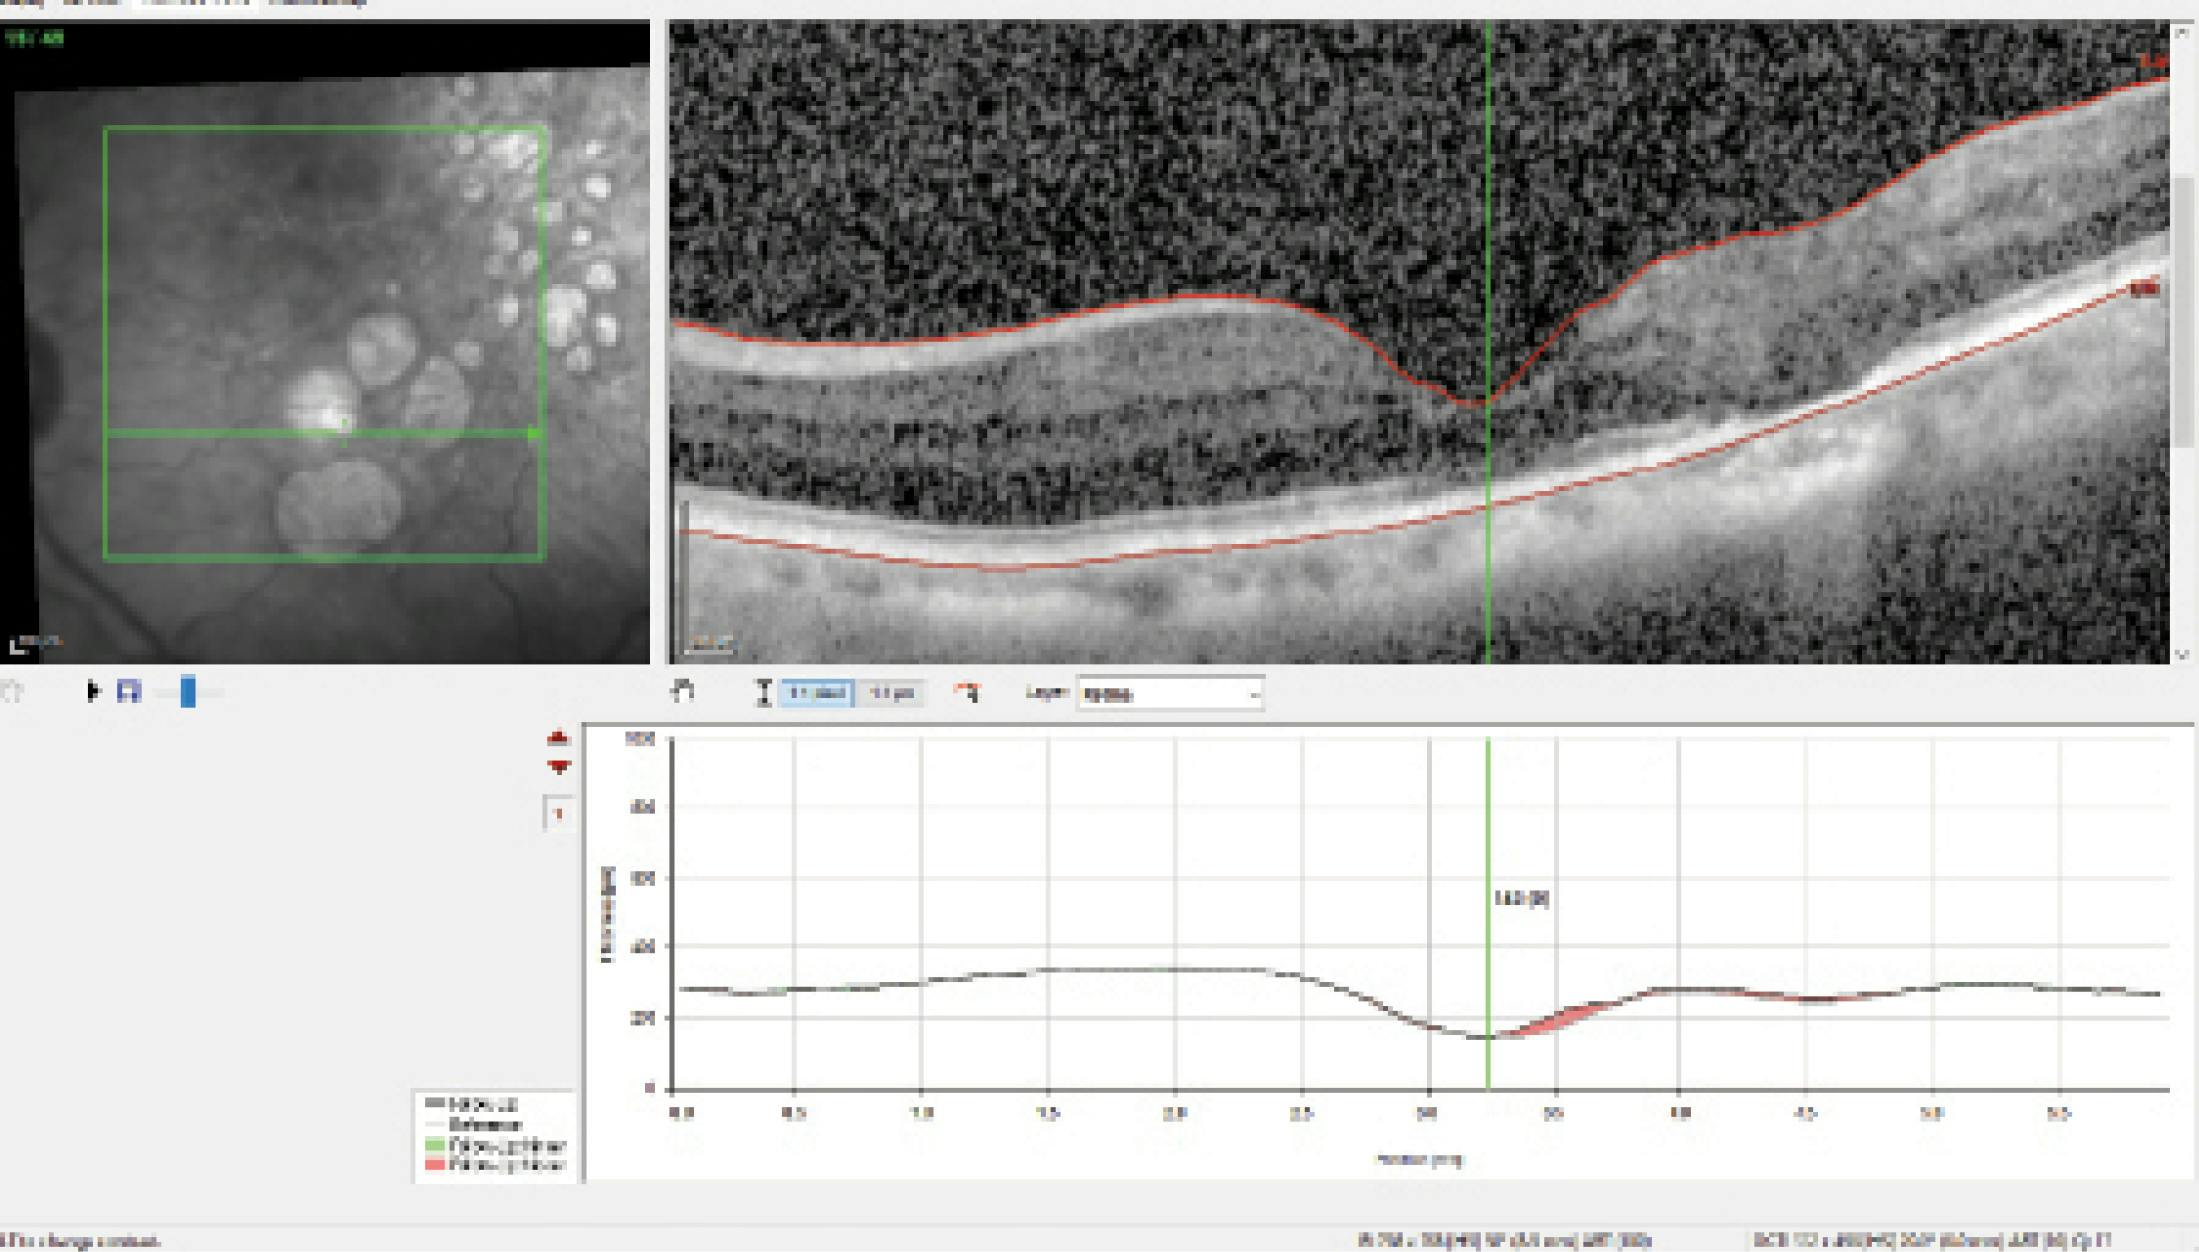

Dr. Radcliffe: A patient who has been followed in my practice is developing two diseases: cataract and GA. Initially, visual acuity was 20/40, but the foveal OCT (Figure 1) was concerning. Dr. Kitchens, why does the fovea look this way?

Dr. Kitchens: The reference image shows big punched-out areas of GA, and it looks like the green arrow is going right through the fovea. The cross-section shows a foveal depression. That leads into not only atrophy of the retinal pigment epithelium and increased signal transmission, but also atrophy of the retina, indicating an advanced stage of GA. A thorough conversation about IOL options and expectations for cataract surgery is warranted. This patient will not be happy if they invest in a premium IOL and 6 months later they are seeing 20/100.

Dr. Ristvedt: Because the atrophy is so close to the fovea, it would be interesting to use fundus autofluorescence to evaluate any areas of hyperfluorescence, indicating progression. I do think that this patient could be a candidate for a nondiffractive, astigmatism-correcting IOL.